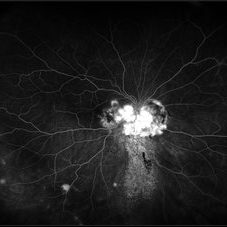

Central Retinal Vein Occlusion with Severe Ischemia

Composite fluorescein angiogram of the left eye of a male with a Central Retinal Vein Occlusion with severe ischemia.

Photographer: Olivia Rainey

Imaging device: Heidelberg Spectralis

Condition/keywords: central retinal vein occlusion (CRVO), composite, fluorescein leakage, ischemic CRVO